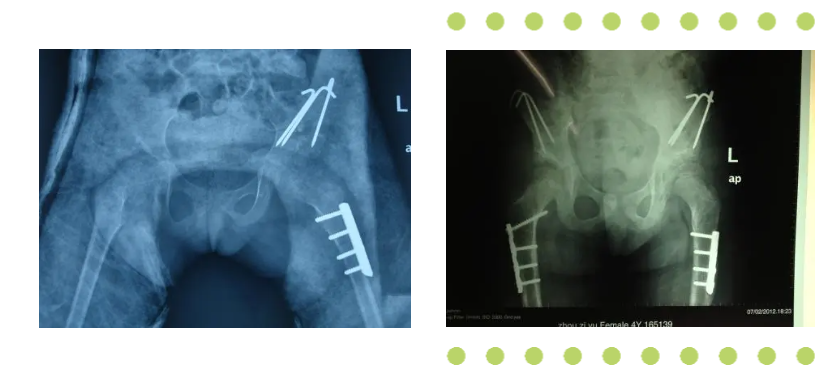

發(fā)育性髖關(guān)節(jié)脫位

Pavlik吊帶、石膏褲衩固定、切開(kāi)復(fù)位、骨盆及股骨轉(zhuǎn)子下截骨等